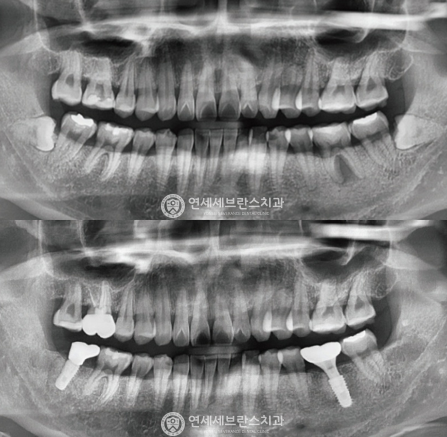

03

전악 임플란트

치아가 하나도 없거나 심각한 구강질환을 앓고 있어도

전악 보철을 제작, 임플란트를 치조골에 식립해

기능적, 심미적으로 자연치아와 가장 유사한 수준으로 재현이 가능합니다.